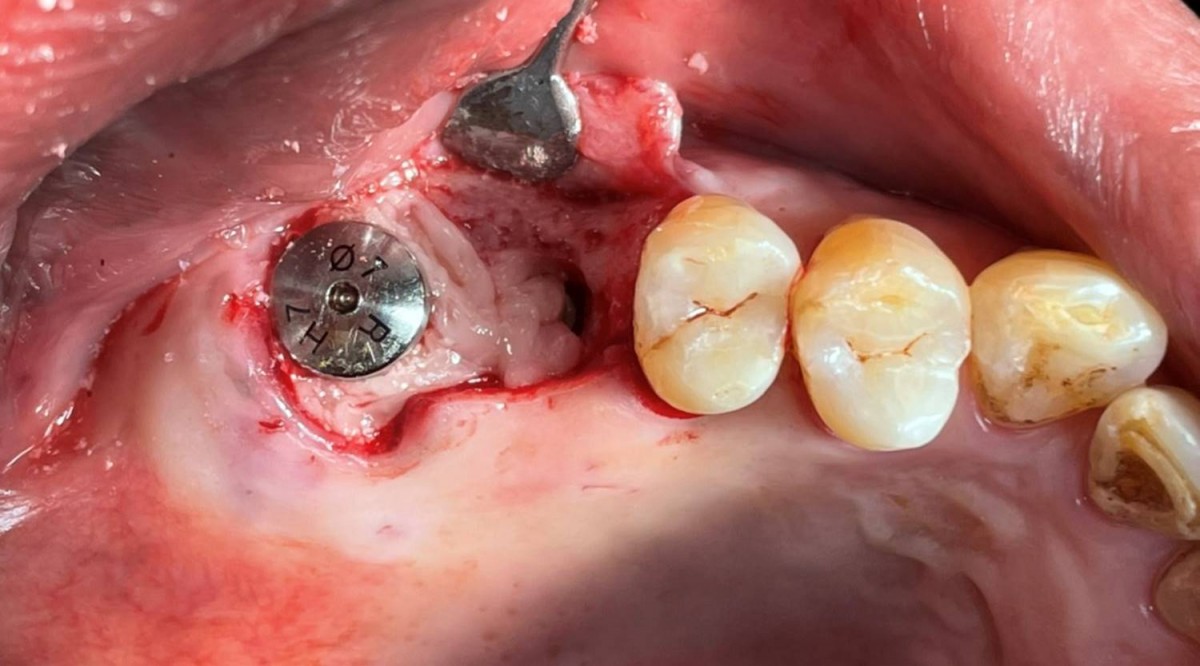

Maxillary Sinus Graft, 2 Implants, Crown Contouring

<GCaks> A 56-year-old male patient had pain-inducing caries, and perio-involved tooth mobility resulted in a tooth fracture at 1st molar. And it was removed months ago. He was a heavy smoker and showed poor oral hygiene.